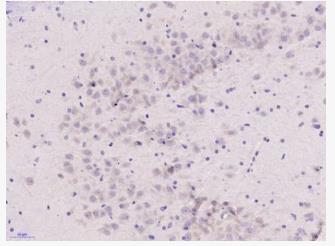

- WB=1:500-2000 IHC-P=1:100-500 IHC-F=1:100-500 (石蜡切片需做抗原修复) not yet tested in other applications. optimal dilutions/concentrations should be determined by the end user.

- WB=1:500-2000 IHC-P=1:100-500 IHC-F=1:100-500 (石蜡切片需做抗原修复) not yet tested in other applications. optimal dilutions/concentrations should be determined by the end user.